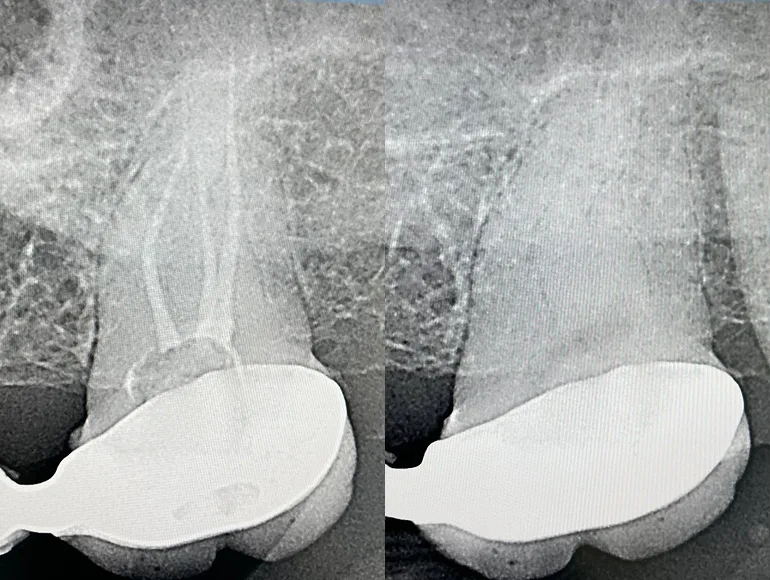

Rootcanal therapy through dental prosthesis

Case by Dr. Taha Azimaie: Retreatment of rootcanal through dental prosthesis can save patient money and dental visits. This tooth endodontically treated and was part of a dental bridge. The tooth also contained a long pin (AKA post) that is cemented deep in the canal, removal of a post is a challenging procedure and can lead to tooth fracture. In this case, an access hole made through the bridge and post removed. Root canal therapy retreated and the access hope filled with dental filling material. Now this dental bridge can last longer and may not require replacement.